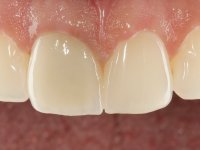

The patient came to the consultation because she did not like the “dark line next to the gums” that she had on her upper right central incisor.

Female patient, 33 years old, non-smoker. Tooth 11 with endodontic treatment rehabilitated with a crown. This crown shows an infiltrated cervical interface. The smile line was high, this area being very visible. The patient had a thick gingival phenotype and good oral hygiene.